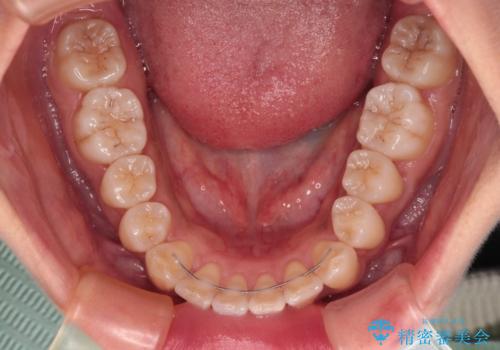

奥歯の咬み合わせ改善後に、インビザラインにて歯列を整えることとしました。

カリエールディスタライザーを併用したことで、確実かつ短期間で治療を終えることができました。